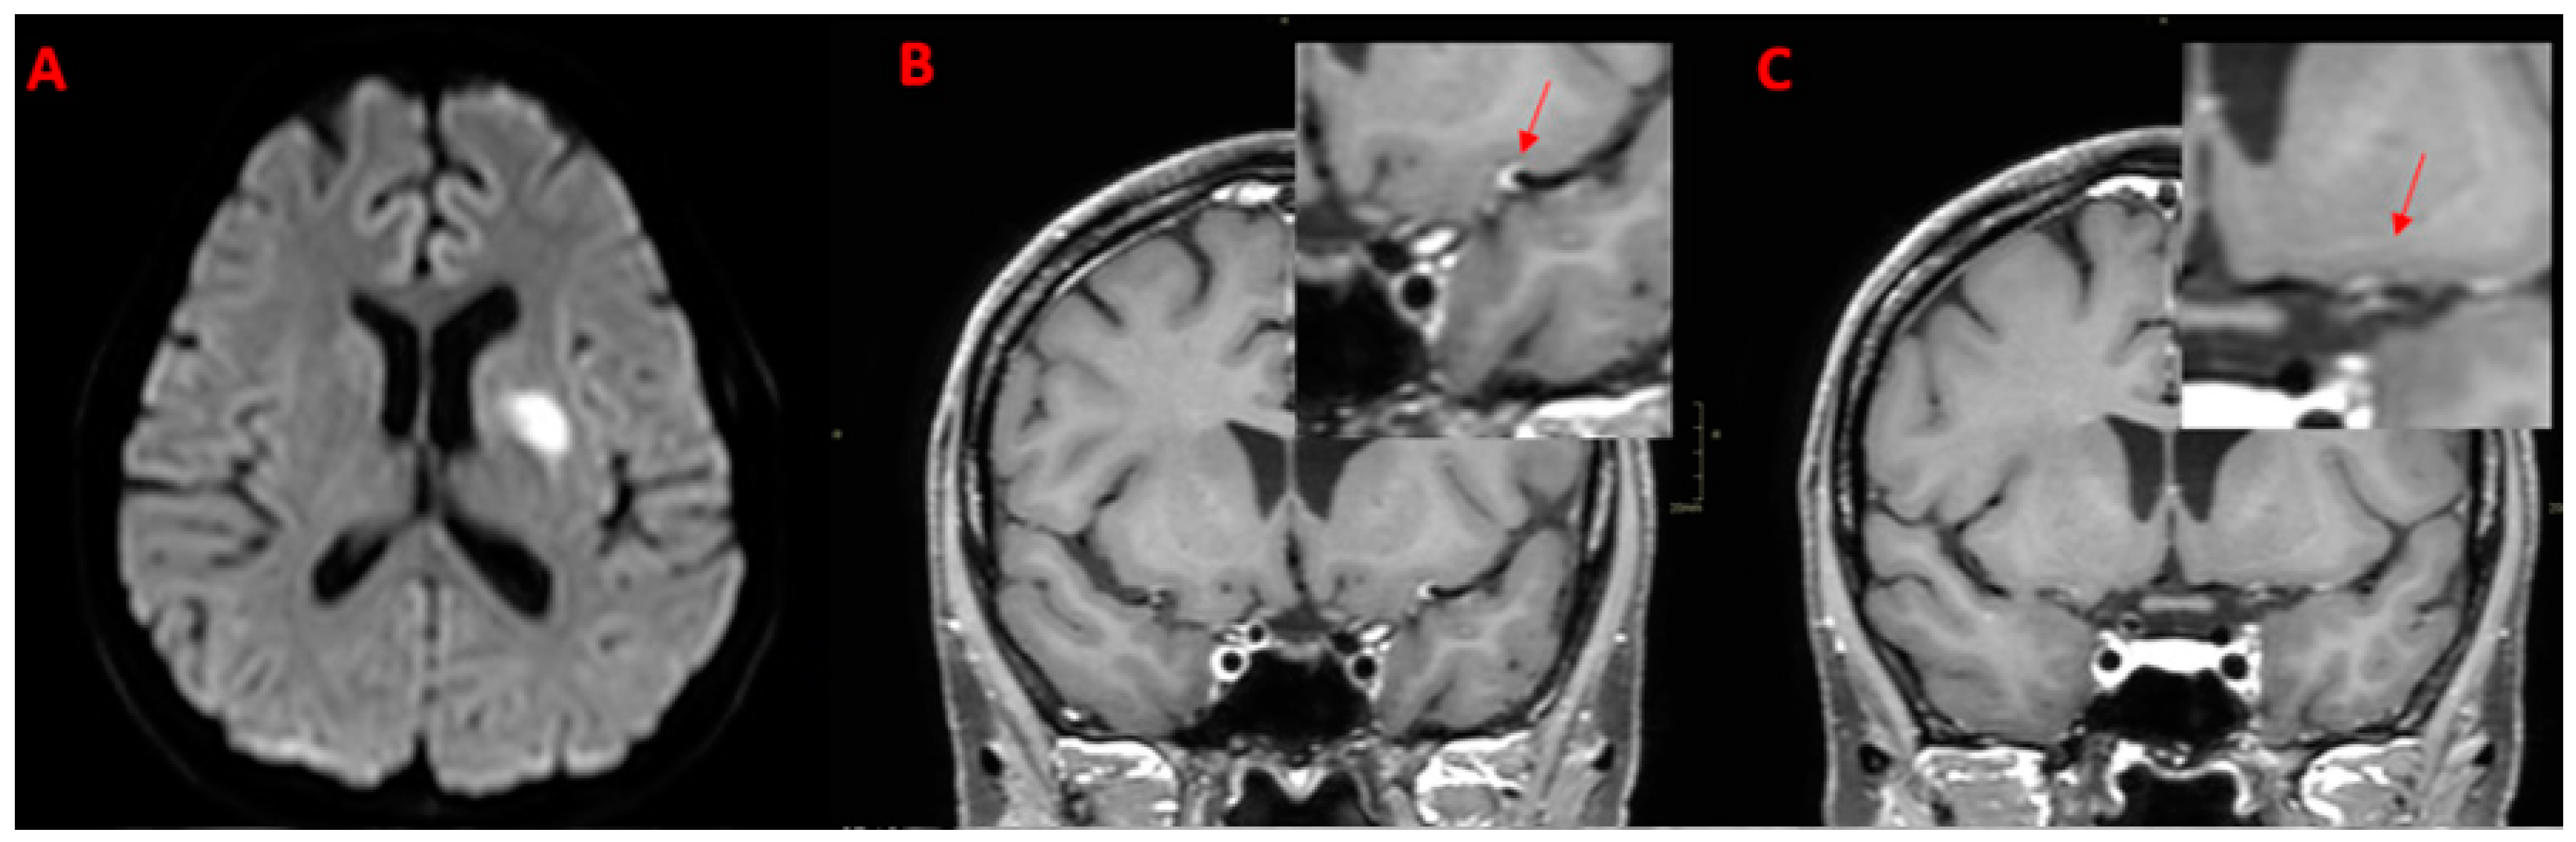

7. Legend

| 66Y, M | 3 | Present | Present | Bilateral Basal Ganglia, Left SCA | SCA | ACM (M1) ICA BA | Present | Subtentorial |

| 32Y, F | 1 | Absent | Absent | No | None | None | Absent | // |

| 49Y, M | // | Absent | Absent | No | ACM (M2) | ACM (M2) | Present | Supratentorial |

| 83Y, F | 2 | Present | Present | Cortical-Subcortical in PCA Territory | PCA (P2) | None | Absent | // |

| SCNSV Systemic disease (n = 4) | 3 (75.0%) | 2 (50.0%) | 0 (0.0%) | 2 (50.0%) | 2 (50.0%) | 2 (50.0%) | 3 (75.0%) | 2 (50.0%) | 0 (0%) | 3 (75.0%) | 0 (0%) | BA, VA, SCA, ICA, ACM (M1), PCA (P2) |

| multiple: 3 (100.0%) | ||||||||||||